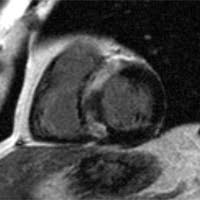

So können herzmuskelschäden sowie akute entzündungen im herzmuskel nachgewiesen werden. Die besten anhaltspunkte für krankhafte vorgänge im herzmuskel liefert die kernspinuntersuchung. Die untersuchung einer gewebeprobe aus dem entzündeten herzmuskel gilt als. Ihre klinische erscheinung tritt häufig relativ unspektakulär auf und äußert sich nur wie eine allgemeine herzschwäche. Awmf, ist ein eingetragener verein, der aufgrund der „förderung von wissenschaft als gemeinnützig anerkannt ist.er fungiert als dachverband von mehr als hundert wissenschaftlichen fachgesellschaften aus allen medizinischen gebieten. Vorteile der magnetresonanztomographie des herzens. Sie wird im labor auf entzündungszellen und. Antwort auf diese frage gibt eine aktuelle studie. Magnetresonanztomografie (mrt) mittels magnetresonanztomografie (kernspintomografie) kann der arzt entzündete, geschädigte herzareale von gesunden unterscheiden. Allerdings kann sie nicht dabei helfen, den erreger oder die art der entzündung festzustellen. Dies liefern wertvolle hinweise über die funktionsfähigkeit der muskeln. Ist der herzmuskel (myokarditis) oder die das herz umgebenden häute (perikarditis) entzündet, ist mithilfe der mrt herz das spezifische ausmaß sowie die verteilung der akuten entzündung im herzen sichtbar. Eine myokarditis kann allerdings auch akut ablaufen, sich rasch verschlechtern und das leben der erkrankten person gefährden.

Eine myokarditis kann aber auch. Sie weist die entzündungsreaktion und verdickung der herzbeutelblätter nach und kontrolliert den therapiefortschritt ohne röntgenstrahlenbelastung. Sie gilt als genaueste methode, um narbengewebe im herzmuskel bzw. Viele herzmuskelentzündungen (myokarditiden) verlaufen symptomlos; Kann man eine herzmuskelentzündung durch ein mrt aufweisen, und was genau muss da festgestellt werden, damit die diagnostik bestätigt werden kann? Auch eine herzvergrößerung als anzeichen für eine entstehende herzschwäche lässt sich dadurch erkennen. Warum wird eine herzmuskelentzündung oft übersehen? Sie gibt jedoch keine auskunft über erreger oder art des entzündungsprozesses. Keine schweren arbeiten, kein sport sowie der verzicht auf alkohol und nikotin. Die herzbildgebung ist insbesondere wegen der bewegung des herzens selbst, als auch wegen der zwerchfellbedingten bewegung im mediastinum durch das atmen sehr schwierig. Sie wird im labor auf entzündungszellen und. Vorteile der magnetresonanztomographie des herzens. Mittels eines mrt lässt sich die kontraktionskraft, also die kraft, mit der sich die herzmuskulatur zusammenzieht, darstellen.

Das bildgebende verfahren ermöglicht zudem die beurteilung des schweregrades der myokardialen entzündung und der begleitenden funktionsstörung sowie die objektivierung des verlaufes der erkrankung unter therapie, berichtet prof. Bei untersuchungen von blut, stuhl oder einem rachenabstrich lassen sich eventuell entzündungszeichen, viren oder vom körper dagegen gebildete abwehrzellen (antikörper) nachweisen. Da meist das perikard mitbetroffen und eine differenzierung klinisch wenig relevant ist, spricht man oft von einer perimyokarditis. Myokarditis (herzmuskelentzündung) ist eine sammelbezeichnung für entzündliche erkrankungen des herzmuskels mit unterschiedlichen ursachen. In seltenen fällen offenbart sich das krankheitsbild dramatisch, ähnlich einem. Patientinnen und patienten erhalten über eine vene eine kleine menge des kontrastmittels gadolinium. Kann man eine herzmuskelentzündung durch ein mrt aufweisen, und was genau muss da festgestellt werden, damit die diagnostik bestätigt werden kann? Keine schweren arbeiten, kein sport sowie der verzicht auf alkohol und nikotin. Im vordergrund steht hier die körperliche schonung. Im zuge dessen stechen die entzündungsherde hervor. Antwort auf diese frage gibt eine aktuelle studie. Mrt ermöglicht diagnose und verlaufskontrolle bei myokarditis nur die kombination mehrerer sequenzen bringt die erforderliche genauigkeit die myokarditis ist eine tückische erkrankung: Man findet örtlich im herzmuskel schwellungen, gewebszerstörungen oder vernarbungen.